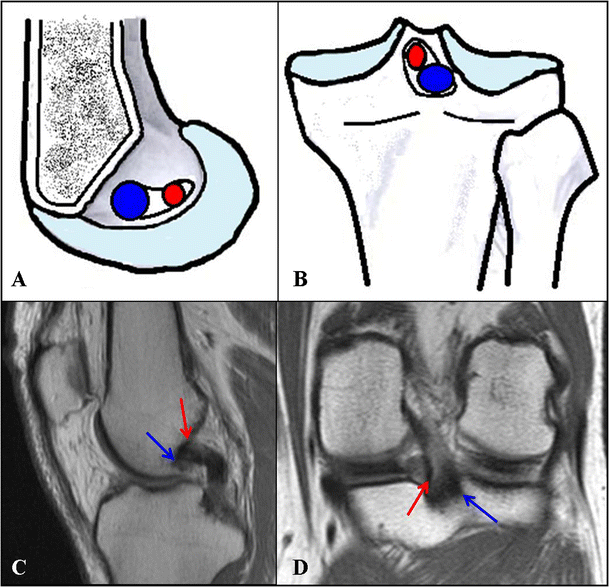

Gross anatomy the pcl attaches to the posterior intercondylar area and passes anterosuperiorly to insert into the lateral surface of the.